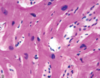

Hypertrophic cardiomyopathy (HCM)- Cause, Gross and microscopic features?

Most common cause of sudden death in young people (familial).

- autosomal dominant disease of the heart muscle

- affected genes include β-myosin heavy chain (most common), myosin-binding protein C, cardiac troponin T and I, α-tropomyosin, actin, titin, and myosin light chains

- Gross- asymmetric septal hypertrophy with a small left ventricular cavity

- Micro- -myocardial disarray consists of short runs of severely hypertrophied fibers